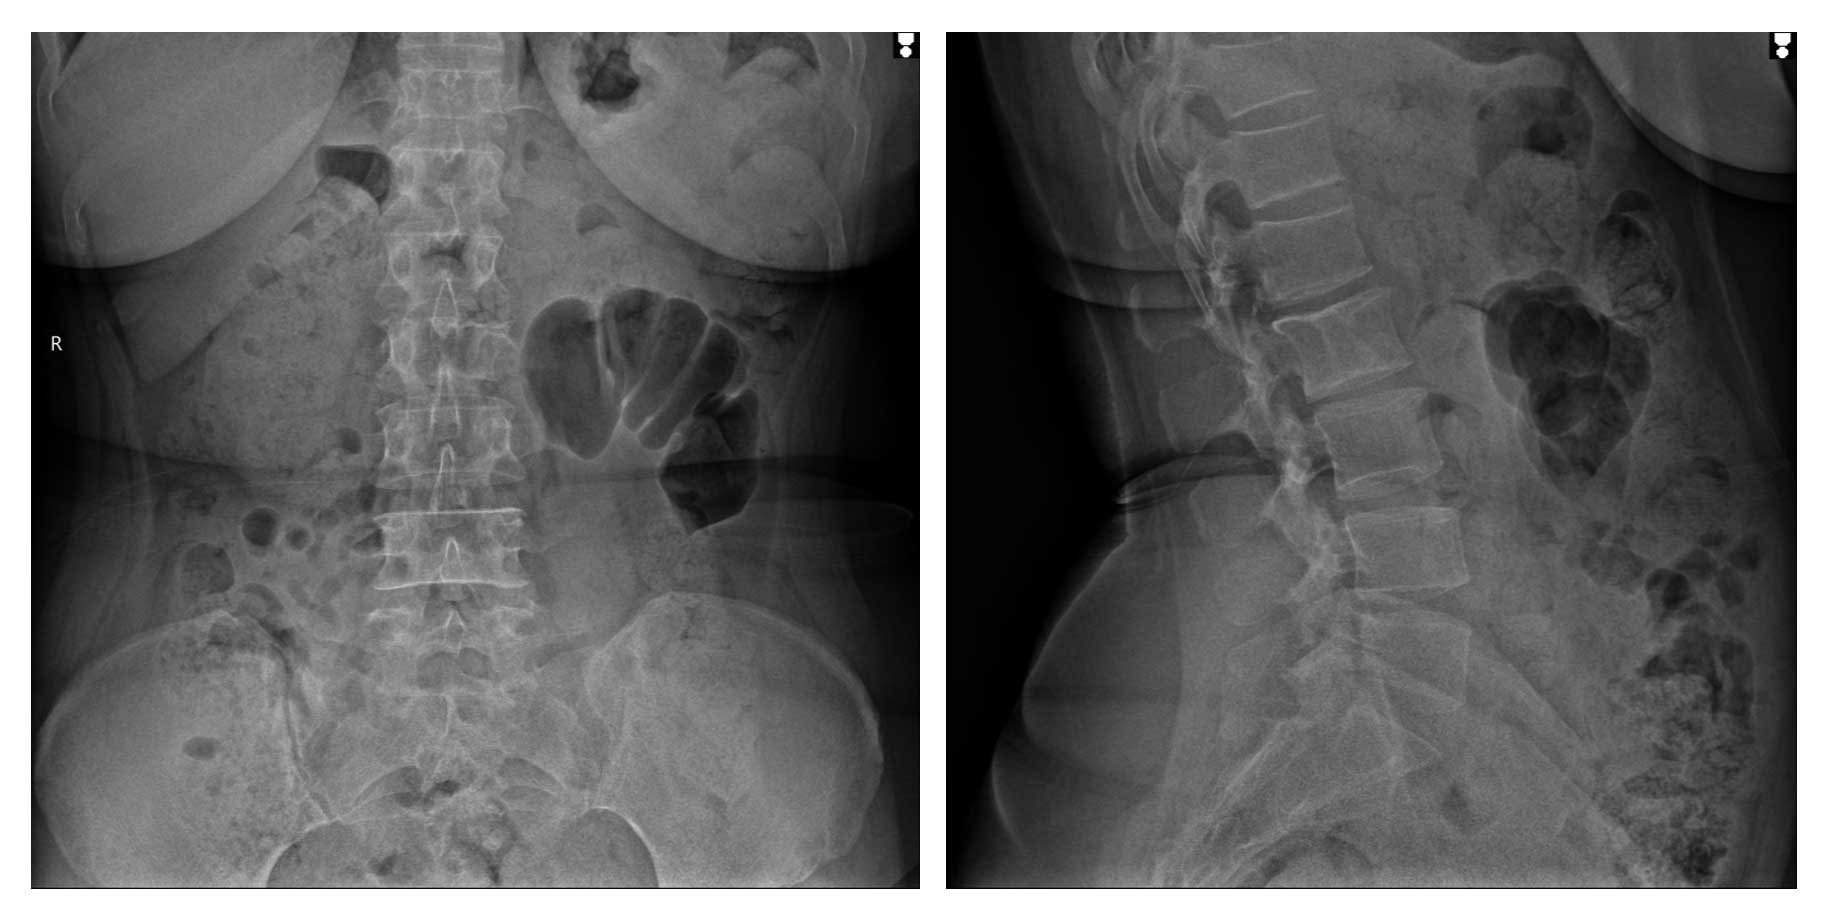

Ameliyat Öncesi: Röntgende L3 vertebrada litik lezyon görülmekte.